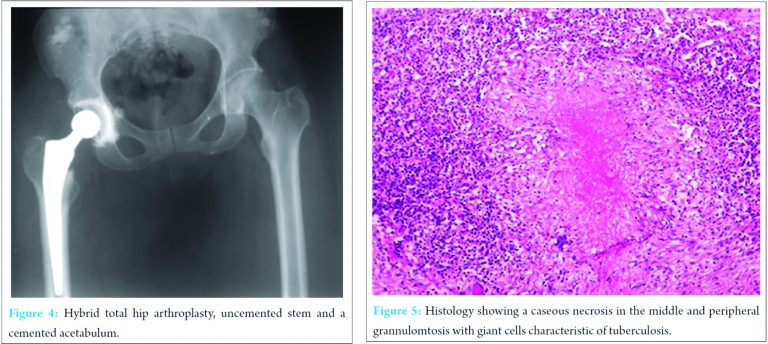

The patient was operated for implantation of a THA via the Hardinge approach. During surgery, an incident was encountered while dislocating the hip to resect the femoral head. There was a cream-white liquid that was oozing out of the hip joint (Fig. 2). A sample was rapidly collected per-operative and sent for urgent bacteriological analysis. The gram coloration was negative, the rest of the liquid was then sent for microbiological, mycobacteriological and histological analyses. The debris from reaming and the femoral head (Fig. 3) were also sent for analysis. The surgery was continued and completed with the implantation of a hybrid THA due to the fragile acetabulum; the stem was uncemented while the acetabulum was cemented (Fig. 4). The anatomopathological findings showed an active TB infection (Fig. 5).